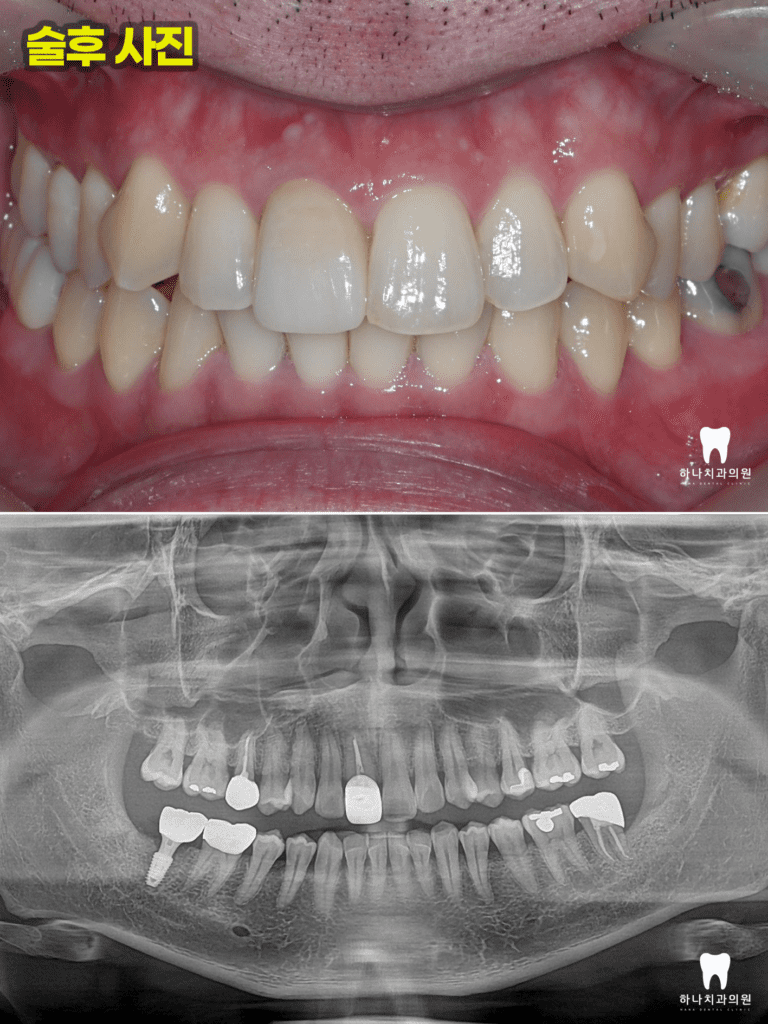

이제는 안 아프고 먹는데 아무런

문제가 없어요~라고 하시며

무서워하지 않고 울산삼산동치과

하나치과의 정기 검진을 잘 받으시겠다는

약속을 해주셨습니다.

하나치과도 환자분의 건강한 치아가

오래 유지 되도록 최선을 다하겠습니다.